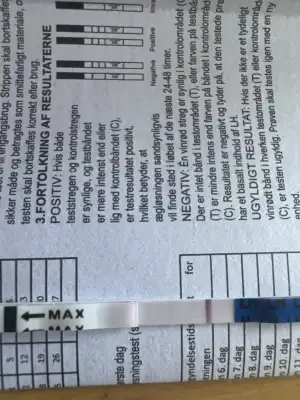

merhaba aranızda hiç ovülasyon veya çatlama gününde göğüslerinde kırmızı çatlak izleri oluşan oldu mu? ben en az 2 kez buna denk geldim ve lh testi ile doğruladım. beyaz çatlak izlerim zaten hep vardı ama ovülasyon gününde kıpkırmızı olup ertesi gün tekrar beyaz oluyorlar. böyle bir şey yaşayan var mı? :)